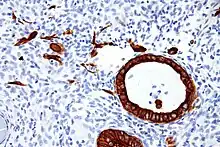

Expression of these cytokeratins is largely organ or tissue specific. The subsets of cytokeratins which an epithelial cell expresses depends mainly on the type of epithelium, the moment in the course of terminal differentiation and the stage of development. Thus a specific cytokeratin expression profile allows the identification of epithelial cells. Furthermore, this applies also to the malignant counterparts of the epithelia, (carcinomas), as the cytokeratin profile is generally retained. Thus the study of cytokeratin expression by immunohistochemistry techniques is a tool of immense value widely used for tumor diagnosis and characterization in surgical pathology.[5]